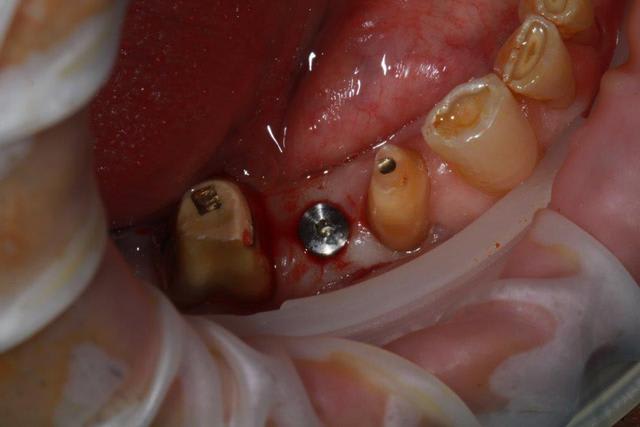

Nouveau patient, pose d'un implant il y a 2 mois....échec sans raisons particulières, douleurs et dépose.

Ce matin repose d'un nouvel implant et comme je ne veux pas prendre de risque, et que les dents adjacentes doivent être couronnées, je pose un bridge en emax press, mais scellé au ciment provisoire...

alors là pas du tout, le patient vient me voir pour des implants, donc je fais une étude du cas absence des molaires supérieures, couronnes mandibulaires très ancienne 45 racine cassée, 44 dévitalisée mais passablement déchaussée, donc avulsion de 45 et pose d'un implant avant de refaire les couronnes 46/47 et l'ensemble.

Échec implantaire, et oui ça arrive, même dans un cas paraissant simple.

Dépose gratuite bien sur et repose gratuite aussi, le bridge n'est pas facturé non plus, il le sera sous forme de 2 couronnes que cette fois ci l'implant fonctionne ce que j’espère, ou laissé en bridge si l'implant devait être retiré.

Le fait de scellé au ciment temporaire ne pose en principe pas de problème pour 3 à 6 mois.

dans le cas présenté, le but est de redonner confiance au patient, et pas du tout le fric.

Oui, un Px, le premier était un Reg.

l'os était tendre, ce qui explique le choix du Px